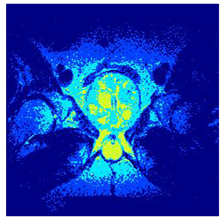

In this subsection, we will discuss the experiment designed to evaluate the performance of EO with cross-entropy for the segmentation of prostate MRI images. To this end, we use a group of reference images formed by a set of six prostate MRI images; see Figure 4. All the images from the group were extracted from the Ferenc Jolesz National Center for Image-Guided Therapy, Harvard Medical School, or Brigham Health Hospital datasets with no additional preprocessing [50]. Prostate MRI images are primarily used for disease diagnosis or to establish treatment for prostate-related diseases such as prostatitis, benign prostatic hyperplasia (BPH), and prostate cancer, among other diseases or medical conditions. In the context of this article, the images were used to test the efficiency of the equilibrium optimizing algorithm and compare it with the other six chosen algorithms. The segmentation of MRIs is carried out over four different thresholds levels: = 3, 4, 5, and 8. Due to the nature of the images, there was a limited number of different tissues in the images; thus, there was no point in evaluating a larger number of .

Figure 4.

Eleven transaxial-cut prostate MRI images. This figure presents a set of eleven transaxial-cut magnetic resonance (MR) images of the prostate. These images serve as the input dataset for evaluating the segmentation performance of the proposed algorithm.

Table 5 presents the segmentation of the MRIs using EO for a qualitative inspection. From Figure 5, it is clear that two lumps in the prostate have been highlighted by the thresholding process. Prostatic MRIs present noisy conditions, which makes it difficult to visualize the thresholding with the naked eye, so in Figure 5 we present the thresholded image as well as the histogram with the values of the thresholds generated by the EO. It can be observed in the histogram that the thresholds present an adequate distribution, even though this particular image has impulsive noise and a simple shape. Our findings indicate that four thresholds are typically sufficient for this application, which corresponds to identifying five different tissue types in the image. A smaller threshold value may result in a lack of sufficient contrast to highlight relevant anatomical structures, such as the prostate capsule. In contrast, a higher number of thresholds may lead to the incorrect differentiation of anatomical regions that should be connected.

Table 5.

Segmentation of transaxial-cut prostate MRI images Using EO and cross-entropy. This table presents the segmentation results of transaxial-cut prostate MRI images using the equilibrium optimizer (EO) and cross-entropy. Each row corresponds to a distinct MRI image, while the columns nt represent the number of thresholds applied during segmentation. The results illustrate the performance of the EO algorithm across different threshold levels for each image.